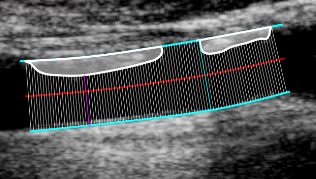

Tracer une plaque

• Dans le panneau Configuration, cliquez sur le bouton Trace the Plaques images/download/thumbnails/388694064/cvs_plaques_button-version-1-modificationdate-1761815630095-api-v2.png .

• Placez le curseur sur le bord où la plaque est fixée et cliquez pour commencer le tracé.

• Déplacez la souris et cliquez pour ajouter des points à la plaque.

• Cliquez avec le bouton droit pour terminer le tracé de la plaque.